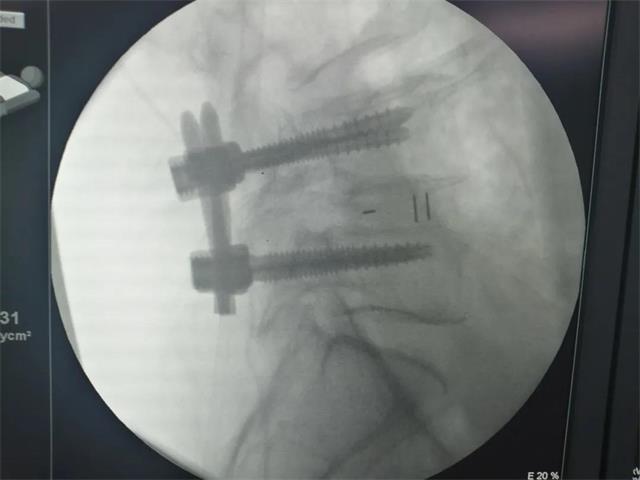

术中融合器(Cage)植入

机器人经皮置钉

术后影像